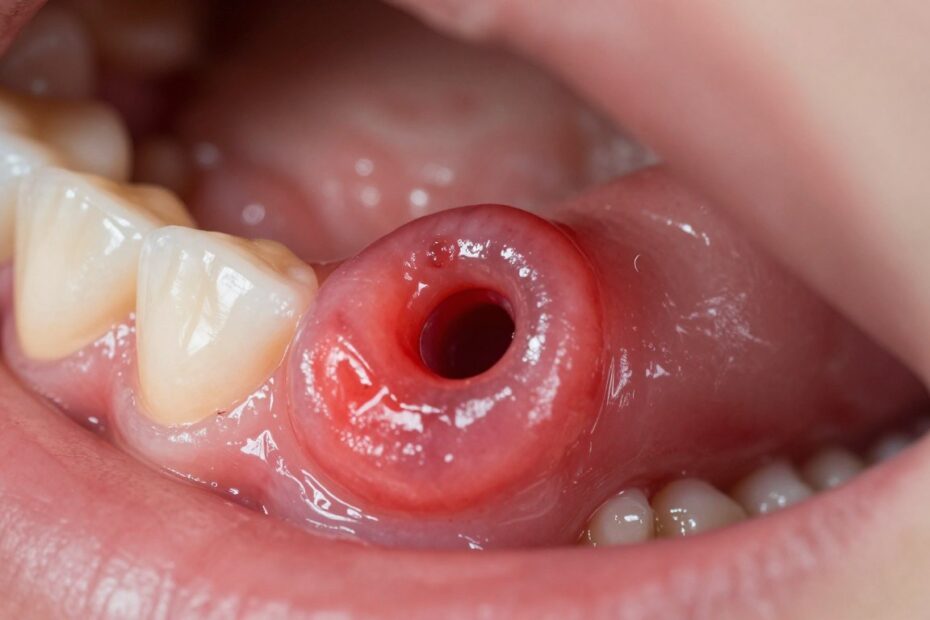

Przetoka zębowa to kanał drenażowy, którym organizm odprowadza ropę z przewlekłego ogniska zapalnego przy korzeniu zęba. W praktyce widzimy małe uwypuklenie na dziąśle, czasem z białawym czubkiem lub widocznym ujściem.

Wyróżniamy przetoki wewnątrzustne i zewnątrzustne. W pierwszym przypadku ujście znajduje się na śluzówce w jamie ustnej, w drugim pojawia się na skórze policzka lub brody.

Istnieją też przetoki aktywne — ze stałym wysiękiem — oraz bierne, które okresowo „się uspokajają”. Brak bólu nie oznacza wyleczenia; bakterii w głębi tkanek nadal może być dużo.

- Jak wygląda: mały guzek na dziąśle z ewentualnym sączeniem ropy.

- Skąd wydzielina: ropna lub krwisto-ropna, wynik zakażenia tkanek.

- Samokontrola: sprawdź w lustrze ujście w jamie ustnej; pojawienie się wydzieliny wymaga konsultacji.